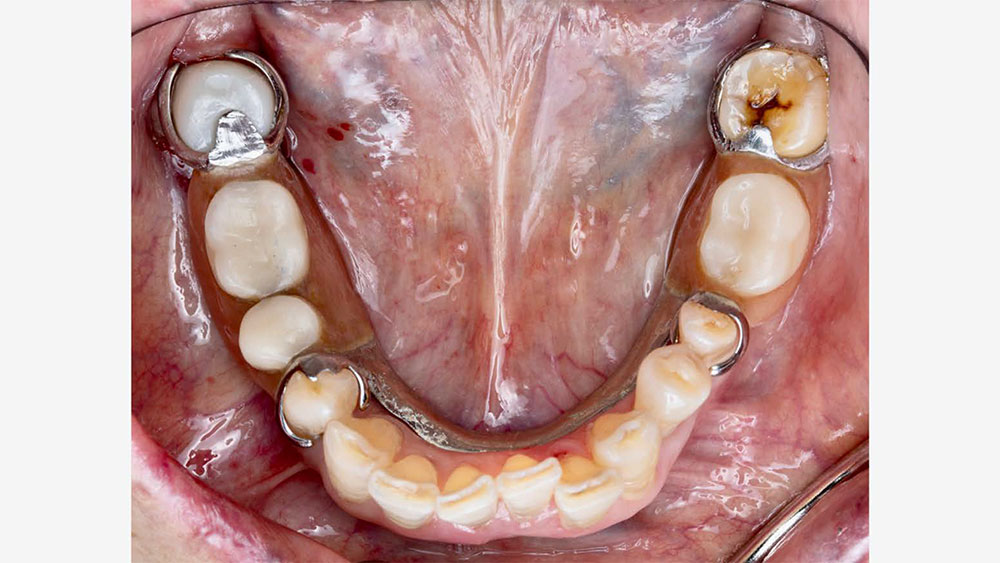

As part of the lab’s quality control process, Glidewell supplies a 3D-printed model and a removable pattern of the partial along with the final crown. This is done in order to check the path of insertion, confirm proper seating and verify engagement with the crown. The photos below show an example of a 3D partial duplicate and model that were supplied with a final crown.

part of the lab’s quality control process